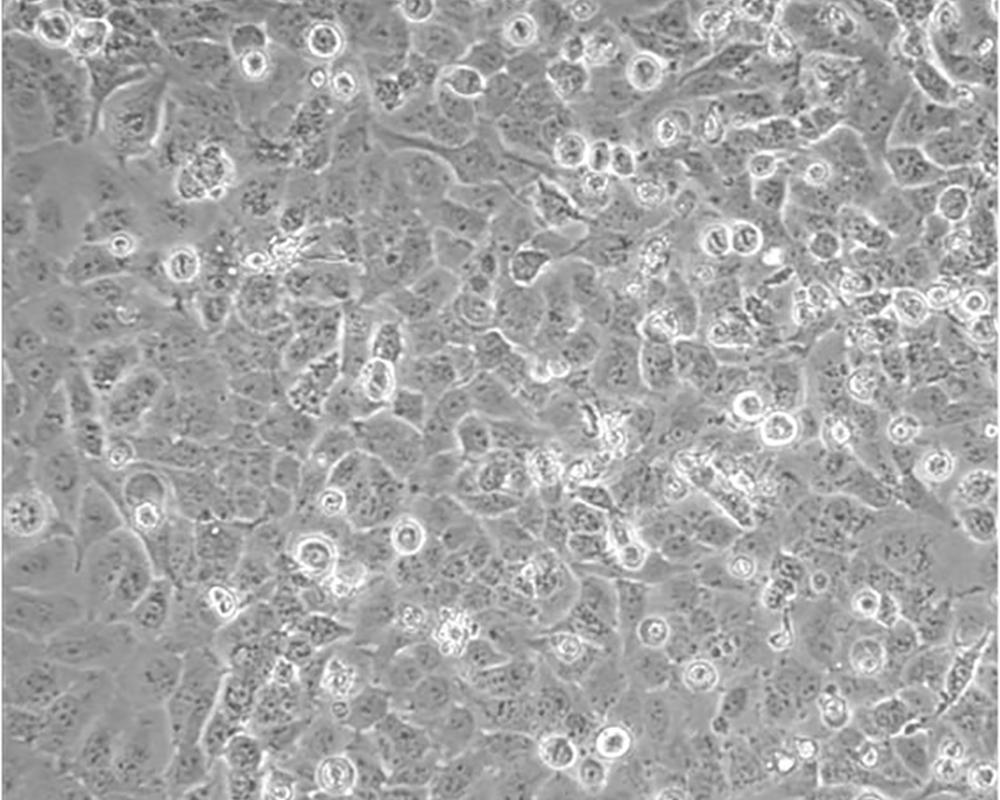

NCI-H23

產(chǎn)品名稱 NCI-H23

組織來(lái)源 肺腺癌;男性

細(xì)胞種屬 Homo sapiens, human

培養(yǎng)基 RPMI-1640+10% FBS+1% P/S

形態(tài)特征 epithelial

細(xì)胞描述 該細(xì)胞源于一位51歲患有非小細(xì)胞肺癌黑人男性患者的治療前的腫瘤組織,表達(dá)C-myc、L-myc、v-src、v-abl、v-erb B、c-raf 1、Ha-ras、Ki-ras、N-ras RNAs;該細(xì)胞攜帶K-ras 12突變;p53基因246位密碼子突變ATC→ATG;表達(dá)PDGF A和B鏈的異源mRNA;表達(dá)TGFα、TGFβ和EGFR;角蛋白 5、8和18陽(yáng)性,波形蛋白陽(yáng)性,神經(jīng)絲蛋白陰性,左旋多巴脫氫酶陰性;據(jù)報(bào)道,在軟瓊脂中該細(xì)胞形成克隆的效率為9.7%。